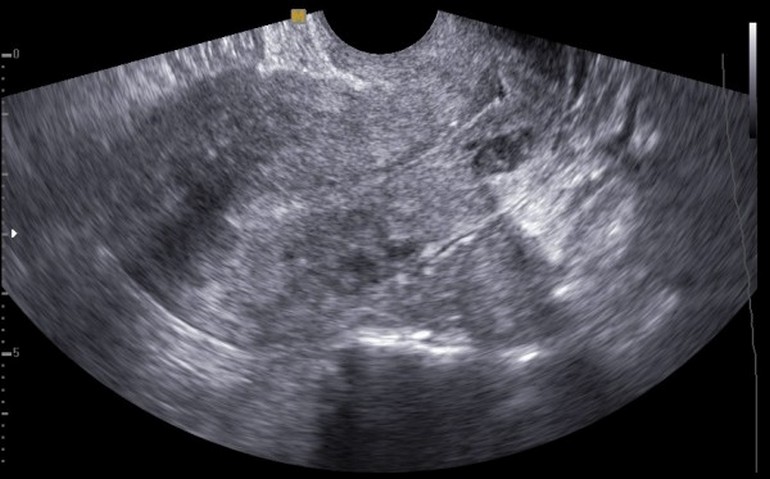

Основным методом диагностики аденомиоза является УЗИ (процедура представлена на фото).

Наиболее точные результаты можно получать при трансвагинальном УЗИ исследовании, которое проводится накануне менструации.

О том, что у пациентки аденомиоз свидетельствует шаровидная форма детородного органа, его увеличение, разница в толщине стенок, а также кистозные новообразования, которые имеют размер 3 мм и больше.

УЗИ при диффузном аденомиозе не столь эффективно, поэтому в этом случае рекомендуется гистероскопия.